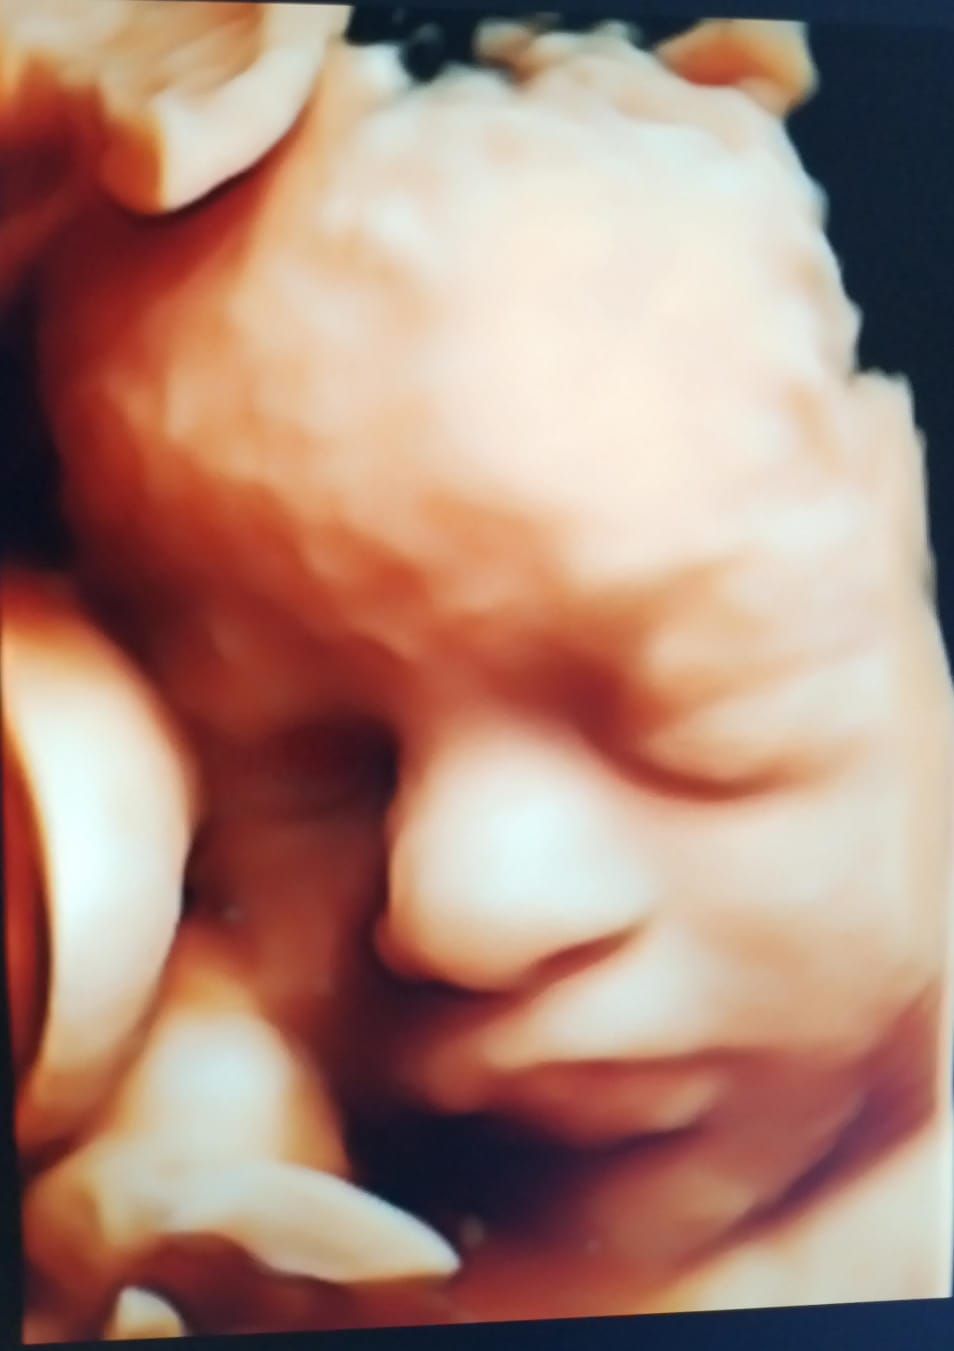

Realizamos ultrasonidos 3D y 4D obstétricos, donde puedes ver en tiempo real a tu bebe así como la evaluación Doppler para determinar el bienestar fetal.

• Ultrasonido 3D

$2,000

• Ultrasonido 4D